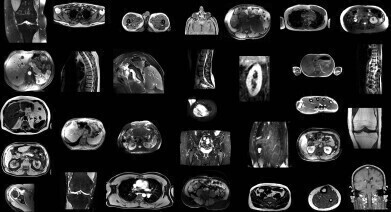

AI model automatically identifies structures from non-sequenced segments of MRI scans. Credit: University Hospital of Basel

Researchers in Switzerland have developed an artificial intelligence (AI) model that can automatically segment major anatomical structures in magnetic resonance imaging (MRI), independently of the sequence in which they were presented to the AI. The model outperformed other publicly available tools in the study.

In the retrospective study, the researchers trained TotalSegmentator MRI to provide sequence-independent segmentations of major anatomic structures using a randomly sampled dataset of 616 MRI and 527 CT exams.

The training set included segmentations of 80 anatomic structures typically used for measuring volume, characterising disease, surgical planning and opportunistic screening.